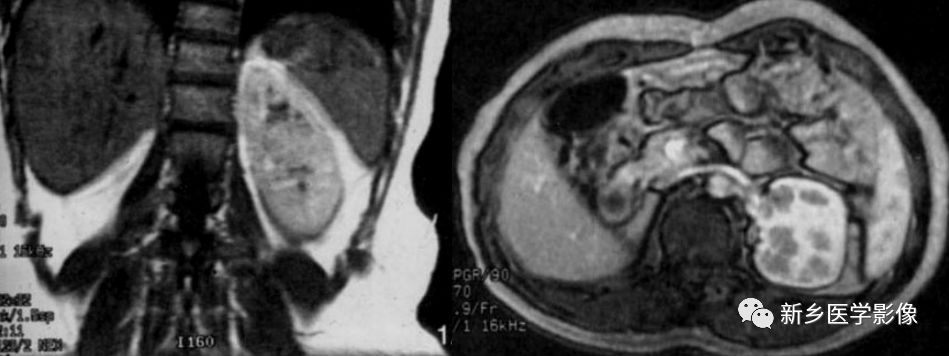

MR特点

双肾下极越过中线,以实质或纤维性连接。合并结石、积水可见不规则T1WI低、T2WI低或高信号,边缘清晰及扩大的肾盂。合并肿瘤可见不规则的T1WI低、T2WI低、高信号,合并出血或坏死可出现 明显T1WI低、T2WI低信号或高信号。冠状面可见拉长的下肾盏结构,可见到起源于主动脉较低水平的多支供血动脉及其他畸形。

其他融合肾(MR冠状面显示好)

➤ 乙状肾:交叉异位的肾位于对侧肾下面,两肾相接,呈S形。

➤ L形肾:交叉异位肾横卧于正常侧肾的下级,肾长轴旋转。

➤ 盘状肾:双肾内缘相对的上下极发生融合,外侧缘形态正常。

➤ 块状肾:双肾广泛融合成不规则形肿块,通常位于骶岬水平。